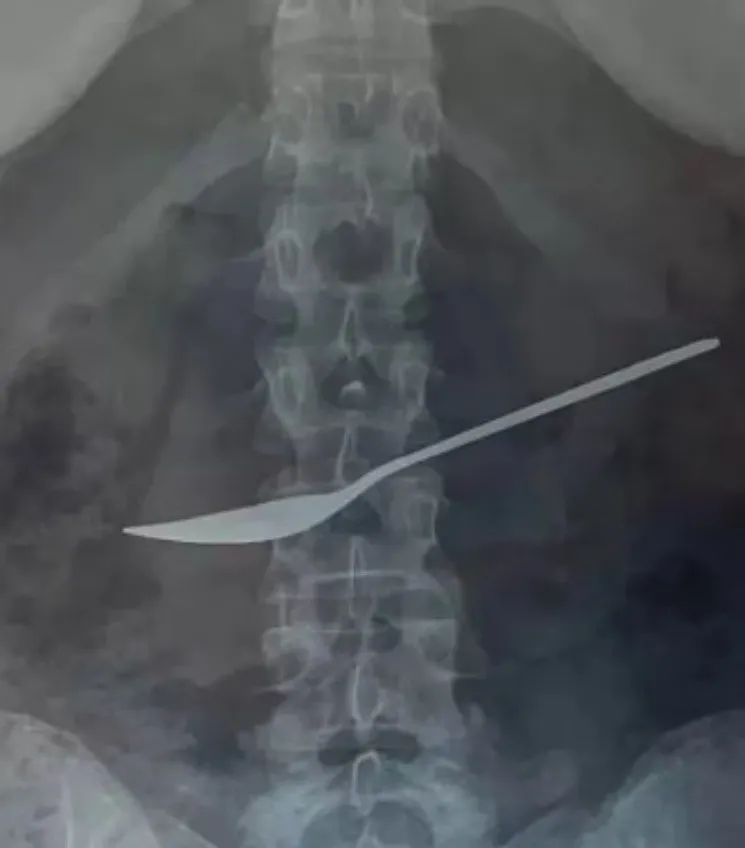

El sorprendete episodio tuvo lugar en la ciudad rusa de Vologda, donde una niña padecía de intensos dolores de estómago, sus padres la llevaron a un nosocomio y los médicos descubrieron la razón.

MUNDO12/05/2024Un particular episodio tuvo lugar en Rusia después de que una nena comenzara a quejarse de un fuerte dolor de panza, por lo cual, sus padres se alertaron al ver que la molestia no se le pasaba y decidieron llevara al hospital Clínico Regional Estatal de Vologda para que recibiera atención médica.

Allí, los especialistas le hicieron estudios y en una radiografía descubrieron algo aterrador: tenía una cuchara alojada en el estómago. Rápidamente, la menor fue sometida a una operación de urgencia para extraer el elemento lo antes posible.

Según explicaron los médicos más tarde, aparentemente la nena se habría tragado la cuchara durante el almuerzo y eso le provocó un dolor en la zona del abdomen. Luego de la extirpar el elemento, revelaron que medía aproximadamente 20 centímetros.

“La niña fue sometida inmediatamente a una esofagogastroduodenoscopia, un examen del estómago con un endoscopio, que ayudó a los médicos a confirmar el diagnóstico”, explicó el médico que la atendió, Dmitry Vankov. Después de ello, se utilizaron herramientas especiales para poder sacar la cuchara a través del esófago.

Al tratarse de una paciente con un buen estado de salud, la operación salió con éxito y la dieron de alta ese mismo día. “Cuídense mucho y manejen con cuidado este tipo de objetos”, alertó Vankov.